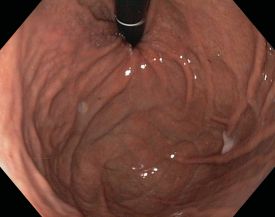

Bei der Gastroskopie (Magenspiegelung) wird der Magen mit Hilfe eines schlauchförmigen Gerätes von innen untersucht. An dessen Spitze befindet sich ein hochauflösender Videochip. Damiti lassen sich außer dem Magen auch die Speiseröhre (Ösophagus) und der Zwölffingerdarm (Duodenum) betrachten, so dass man die Untersuchung häufig auch als Ösophago-Gastro-Duodenoskopie, abgekürzt ÖGD, bezeichnet.

Die Untersuchung erfolgt mit einem so genannten Gastroskop, einem steuerbaren, flexiblen Schlauch, der an ein Videosystem angeschlossen ist.

Die von uns verwendeten modernen Gastroskope haben einen Durchmesser von weniger als einem Zentimeter.

Während der Patient auf der linken Seite liegt, wird das Gastroskop über den Mund in die Speiseröhre eingeführt und weiter in den Magen und Zwölffingerdarm geschoben. Zur besseren Sicht wird Luft in den Magen eingeblasen.